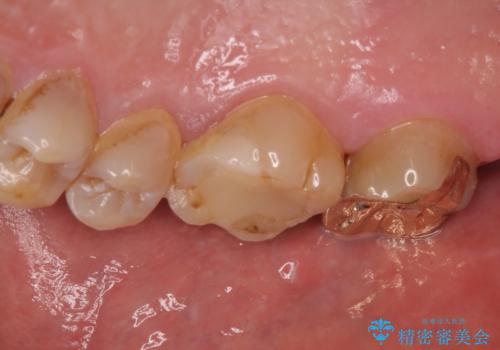

- 銀歯が外れてしまったとのことで来院された患者様です。

上顎奥の粘膜に近い部分で、外れた銀歯の下には大きく虫歯が広がっていました。

虫歯をしっかりと取り除き、ゴールドインレーにて修復することとしました。